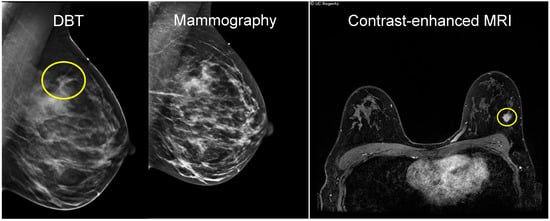

Figure 1.

An invasive ductal carcinoma (IDC) presenting as palpable lump, best seen on tomosynthesis slices of DBT (left), with asymmetry and architectural distortion. The heterogeneously dense breast tissue obscures the finding on the 2D mammographic image (center). Ultrasound (not shown) demonstrated a hypoechoic lesion and was redemonstrated by contrast-enhanced MRI with an irregular mass measured at 1.2 × 1.1 × 1.4 cm (right).

For many years, mammography has been performed utilizing X-ray beam projections resulting in 2D images, which are subject to potential tumor masking by dense breast tissue. Digital breast tomosynthesis (DBT) is a newer type of mammography that collects image data at multiple projection angles while the breast is compressed in standard planes. The resulting reconstructed image is a 3D compressed breast volume []. The volume may also be viewed as a series of individual slices, which enhances lesion boundaries and retains morphological information of masses, thus improving visualization in dense tissue and differentiation between benign and malignant processes []. Compared to 2D mammography, DBT showed a more accurate estimation of tumor size, especially those with diameters < 2 cm and in dense breasts [] (Figure 1). In a study of 51 patients undergoing NAC, tumor size and prediction of pCR were compared among 2D mammography (MG), DBT, ultrasound (US), and MRI. While MRI-measured tumor size had the highest correlation with pathologic tumor size (intraclass correlation coefficients (ICC): MRI = 0.83; MG = 0.56; DBT = 0.63 and US = 0.55), both MRI and DBT were predictive of pCR, more so than mammography and US (area under the receiver operating characteristic curve (AUC): MRI = 0.92; DBT = 0.84; MG = 0.72; US = 0.75) [,].